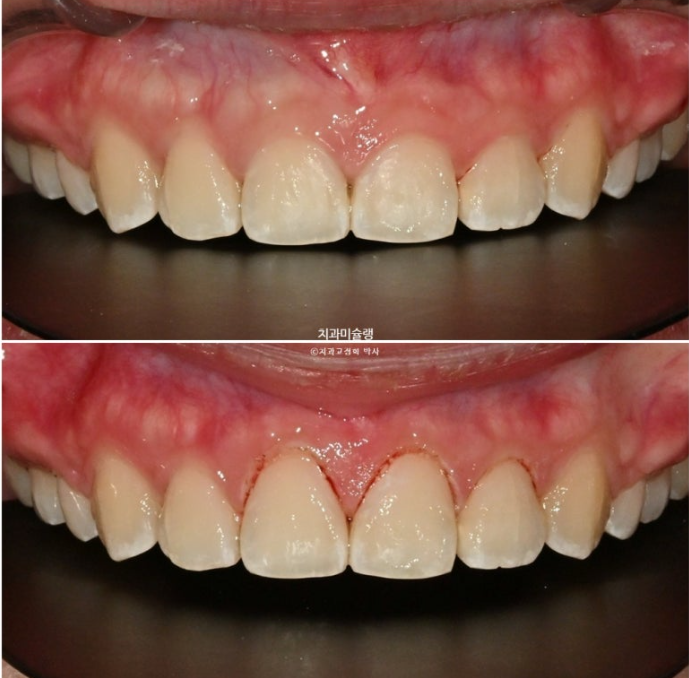

앞니를 합입시키는 과정에서 잇몸이 치아와 함께 잘 따라 올라가기도 하고, 치아 높이가 처음에 비해 짧아지기도 합니다.

후자의 경우는 교정 후 잇몸성형이 필요합니다.

25.11

잇몸성형 직후 모습입니다.

앞니 3개에만 시행했습니다.